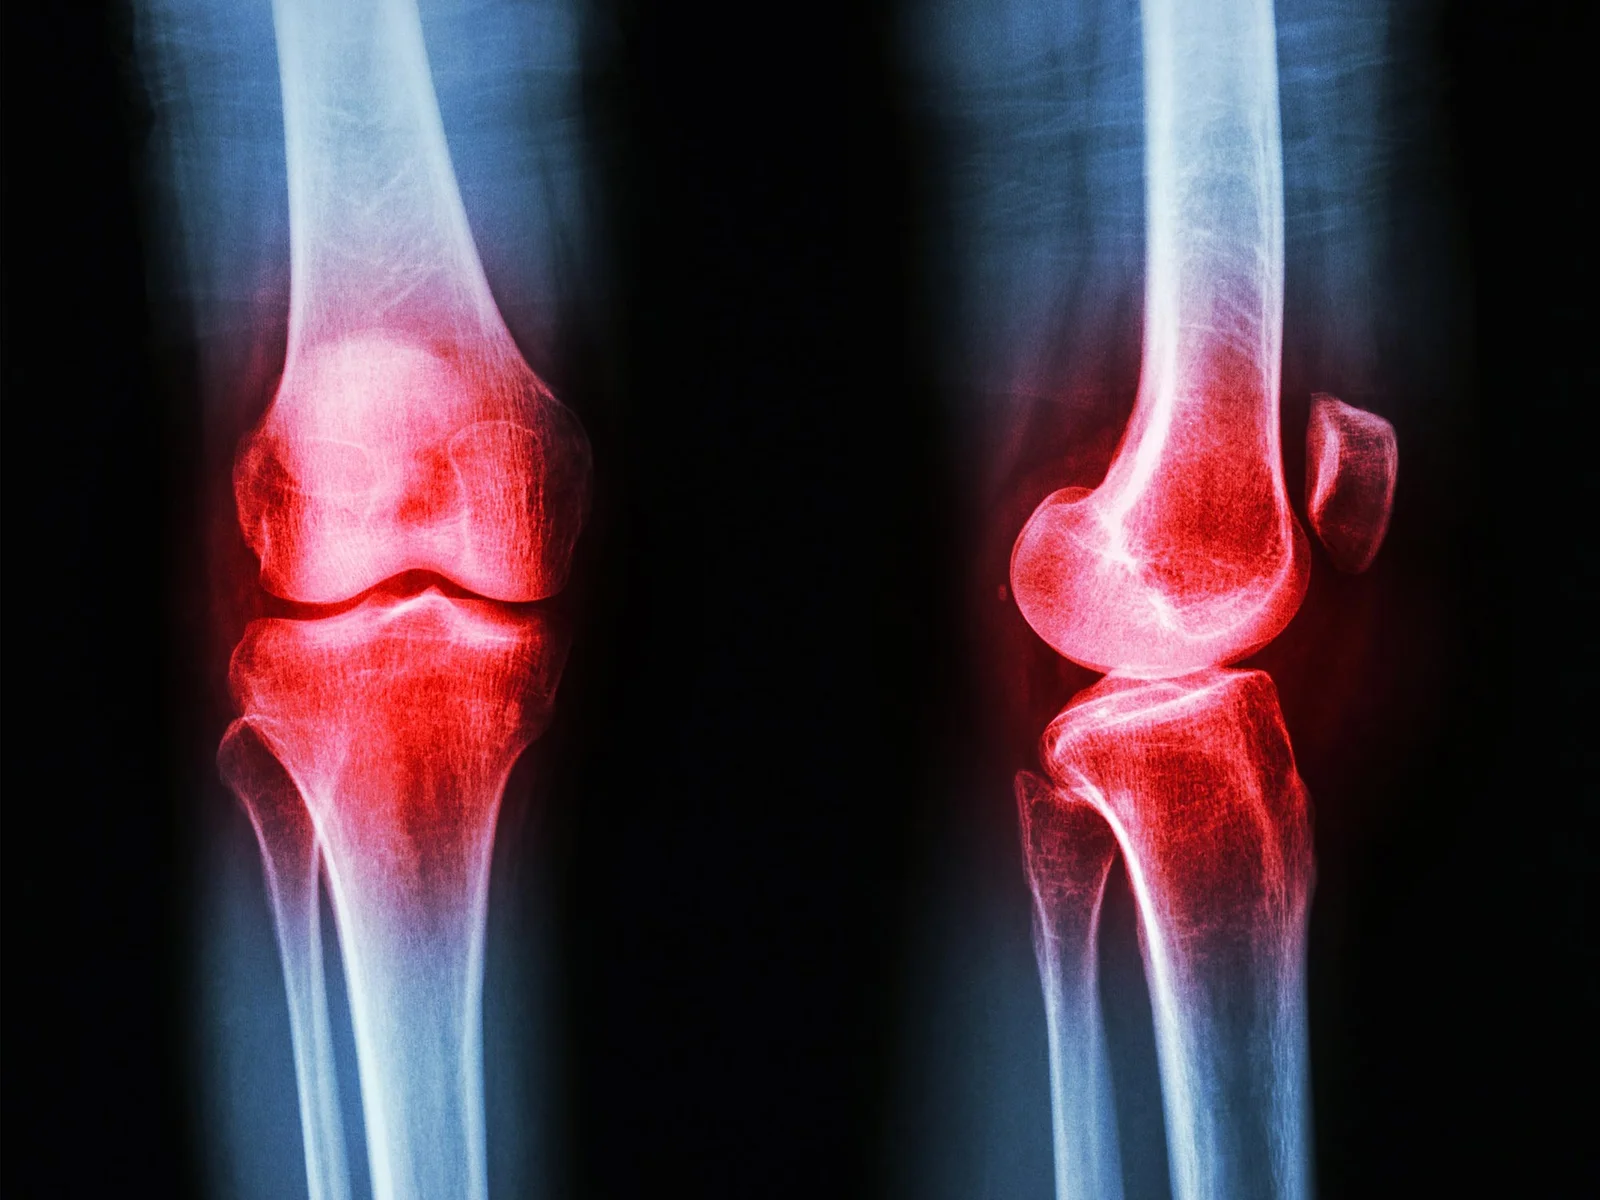

Osteoarthritis Exercise Benefits Are Smaller and Shorter-Lasting, Study Finds

A large umbrella review and data analysis find that exercise therapy for osteoarthritis provides only small, short‑term reductions in pain and function—often comparable to doing nothing in some comparisons—challenging the idea of exercise as a universal first‑line treatment. Effects are smallest for hip and hand OA and diminish further in longer-term or larger studies. While exercise offers other health benefits and may suit some patients, care should be personalized with shared decision‑making, considering alternatives and individual goals rather than universally promoting exercise as the sole first option.